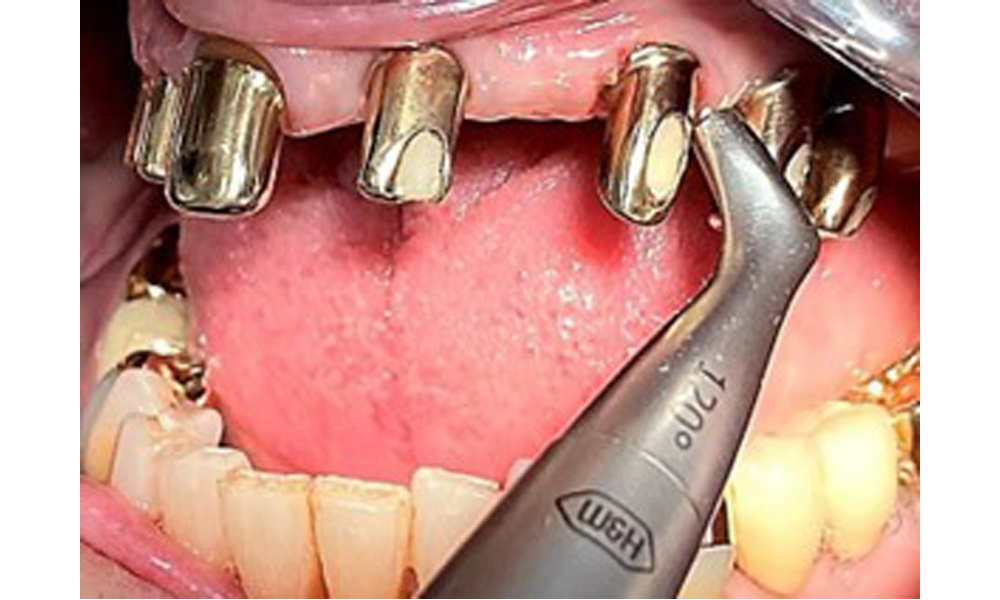

The patient was fitted with a combined removable maxillary telescopic prosthesis more than 25 years ago (Fig. 1, Fig. 2, Fig. 3) and is very happy with her dentures. The patient has an adequate fixed denture for the mandible (Fig. 4).

Frontal view with the maxillary denture in situ.

Fig. 1: Frontal view with the maxillary denture in situ.

The dental findings are as follows: Combined removable implant and tooth-supported telescopic prostheses on implants 15, 13, 21, 23, 24, 25 and tooth 11 (Fig. 1, Fig. 2, Fig. 3). The patient was fitted with a fixed mandibular denture. Adequate bridges were present over 37 to 34 and 45 to 47 (Fig. 4), the crown margins were intact and there were no active caries. A composite filling with a marginal gap was present on tooth 43. There was mandibular gingival recession, exposing 1 to 3 mm of root surface. This also applies to 11.

Occlusal view: Maxilla with tooth and implant-supported telescopic prostheses.

Fig. 2: Occlusal view: Maxilla with tooth and implant-supported telescopic prostheses